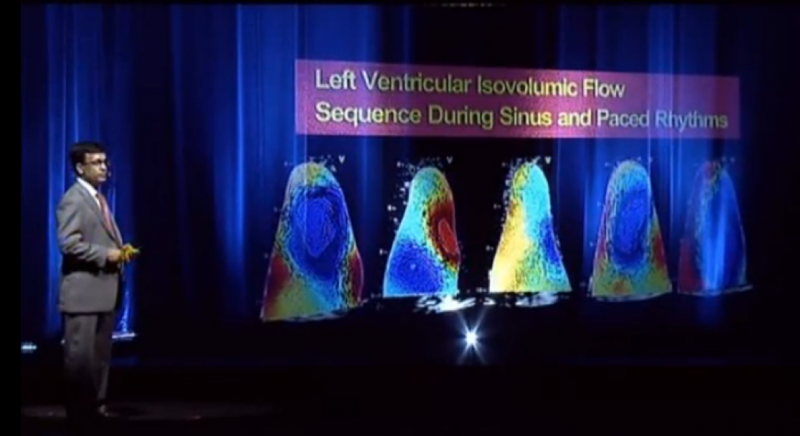

The first-ever presentation at a medical conference using hologram technology instead of traditional video projection screen took place July 1 at the American Society of Echocardiography’s (ASE) 2013 scientific sessions. The innovative presentation was used to drive home the advances in technology that are going to completely reshape cardiac ultrasound and medical imaging over the next few years.